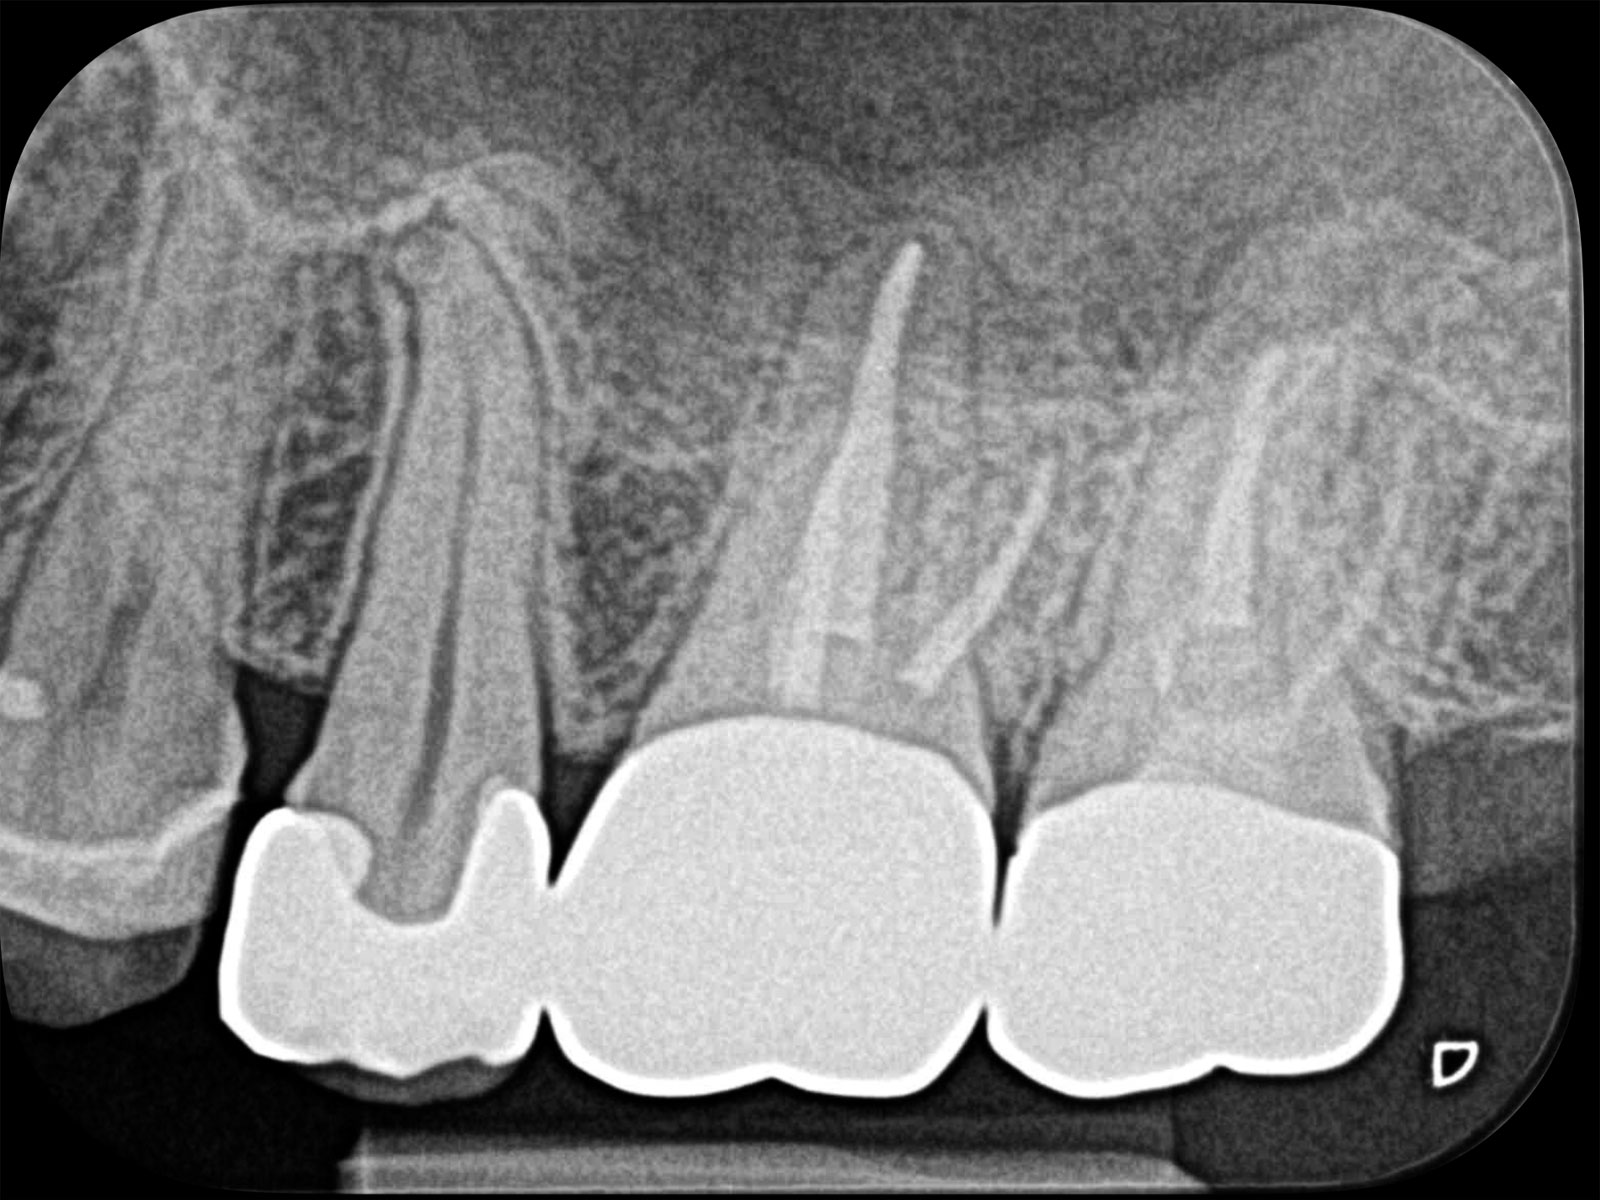

以下が実際に当院で処置した症例です。根管治療で痛みが再発する原因は、細菌が引き起こす炎症です。増殖した細菌が根の先まで進行し、膿がたまります(根尖病巣)。治療後は黒い影がなくなっていることがわかります。

また、治療精度が向上することで、結果的に患者さんの来院回数を減らすことも可能です。